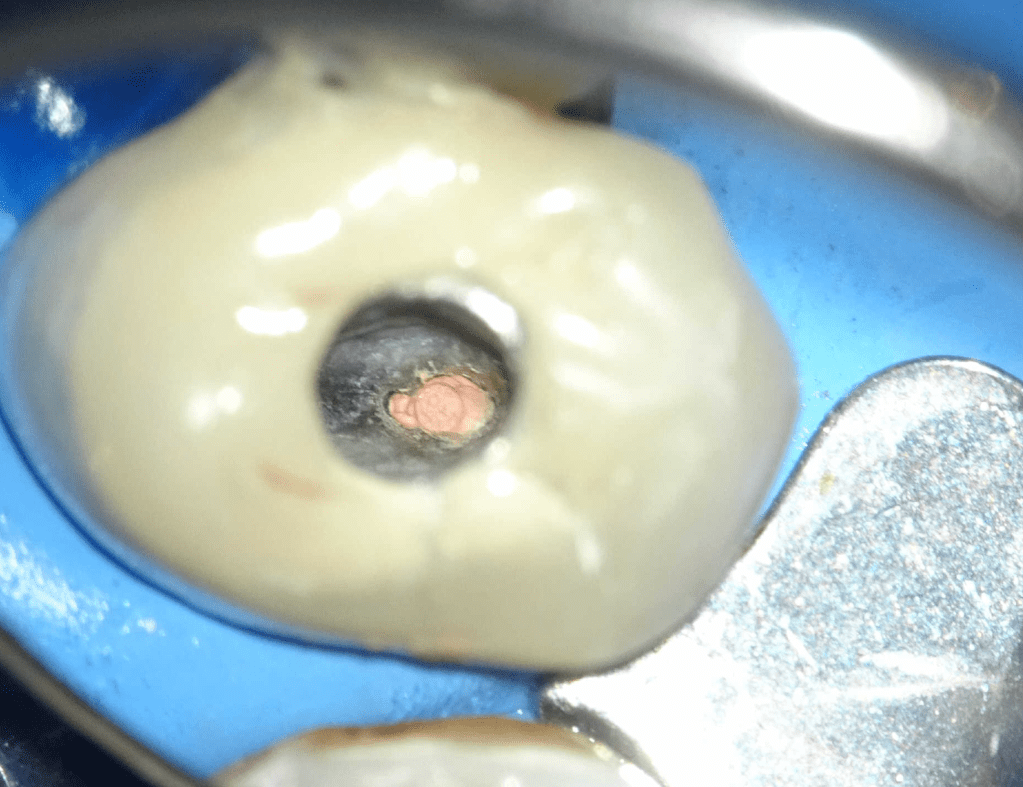

Endodoncias a traves de coronas

20 molar superior a traves de corona